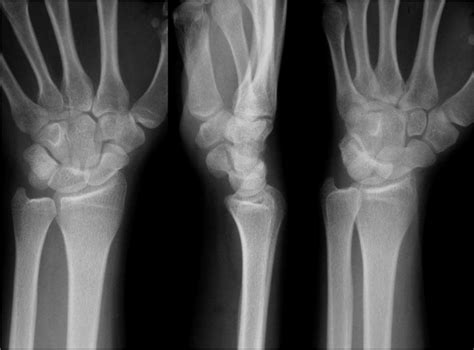

Understanding the intricacies of the human wrist is crucial for diagnosing and treating various conditions that affect this complex joint. One of the most effective diagnostic tools for evaluating wrist injuries and conditions is the Wrist Bones Xray. This imaging technique provides detailed views of the bones and joints in the wrist, helping healthcare professionals make accurate diagnoses and develop effective treatment plans.

A Wrist Bones Xray is a valuable diagnostic tool for evaluating various conditions and injuries affecting the wrist. This imaging technique uses X-rays to produce detailed images of the bones and joints, allowing healthcare professionals to identify fractures, dislocations, and other abnormalities. Some of the key benefits of a Wrist Bones Xray include:

Interpreting the results of a Wrist Bones Xray requires the expertise of a radiologist or orthopedic specialist. The images will be reviewed to identify any abnormalities or injuries. Some common findings on a wrist X-ray include:

• Fractures: Visible breaks or cracks in the bones.

• Dislocations: Misalignment of the bones in the wrist joint.

• Arthritis: Degenerative changes in the joints, such as narrowing of the joint space or bone spurs.

• Bone Tumors: Abnormal growths or lesions in the bones.